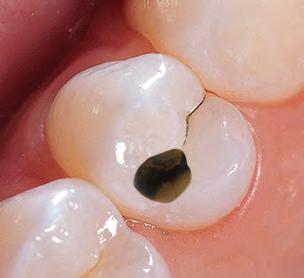

Sable Seek caries indicator contains FD&C dyes, and Seek caries indicator contains D&C dyes in a glycol base. Both are used to stain carious and demineralized dentin.

Seek and Sable Seek caries indicators stain carious and demineralized dentin and can be very useful for difficult-to-see areas, for example; undercuts of preparations, dark dentin, areas along the DE junction, etc. Green Sable Seek caries indicator helps visualization of decay in deep caries cases to help avoid pulp exposures.

PROCEDURE

dentin) with slow-speed round bur or excavator. To control overexcavating near the pulp, remove final portion of caries with hand excavator.